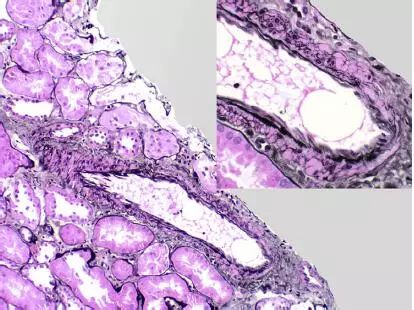

CNI肾毒性导致的血管收缩无形态学变化。急性CNI肾毒性特征包括:近端肾小管上皮细胞空泡化,大小一致;血管损伤,平滑肌细胞丢失;肌细胞胞浆空泡化;细胞坏死或凋亡退化。肌细胞损伤最终发展为局灶性结节性玻璃样变和透明样变,可延伸至小动脉和动脉血管壁整个中层。CNI肾毒性还可引起血栓性微血管病变(TMA),主要累及小动脉和肾小球毛细血管袢。慢性CNI毒性特征为:条状间质纤维化,肾小管萎缩。

图4 CNI肾毒性结节性透明样变延伸至肾小叶间动脉中层(Jones 银染)

图5 CNI肾毒性结节性透明样变延伸至动脉中层(PAS染色)

◆ 条状间质纤维化